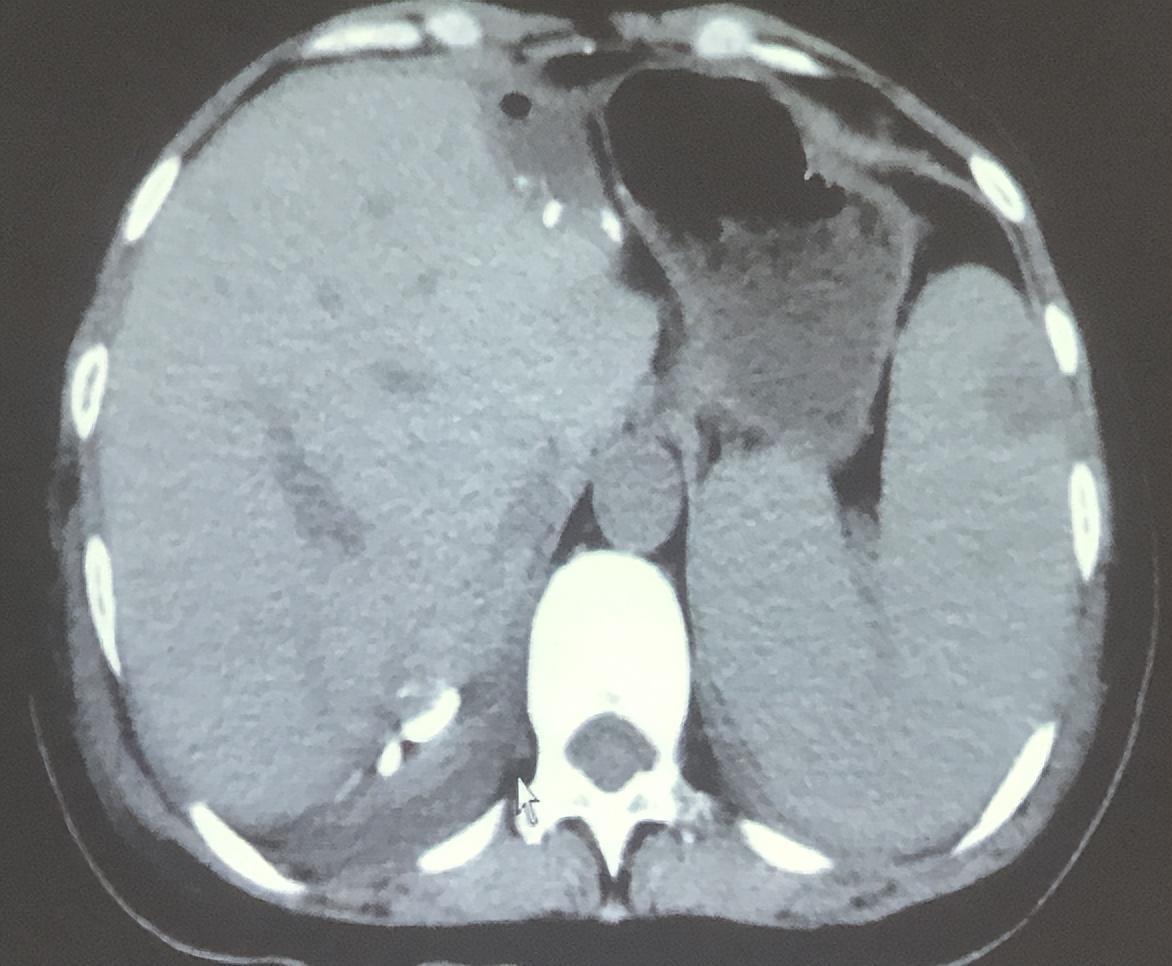

【治疗前影像显示:肝脏有多发转移灶(红圈内)】